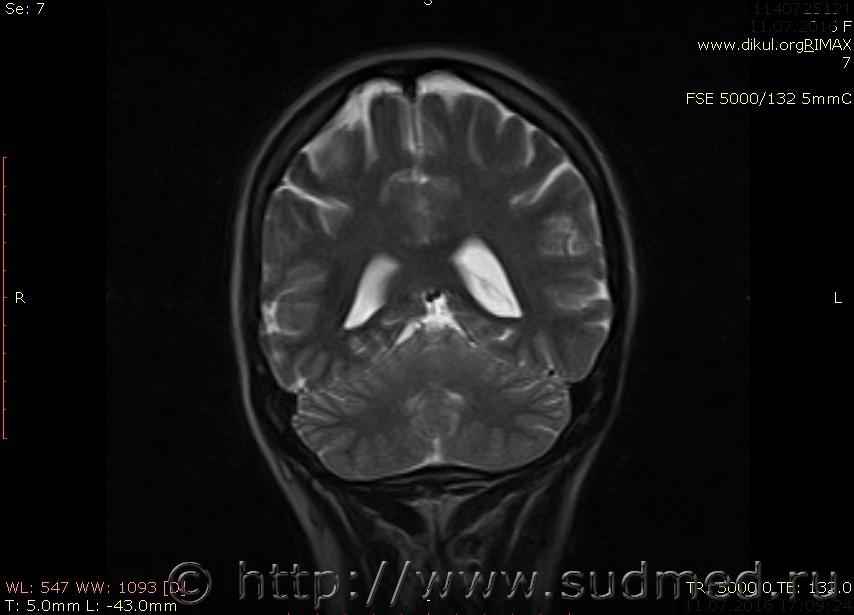

МРТ головного мозга показало: МР-данных за наличие очаговых изменений в веществе головного мозга на момент исследования не выявлено. МР-признаки нарушения соотношения в атланто-осевом суставе. Определяется ассиметрия положения зубовидного отростка С2 относительно боковых масс С1(справа 6,5; слева 4 мм.)

Сама по себе эта информация даёт основания подозревать вывих первого шейного позвонка, но однозначно не свидетельствует о наличии вывиха. Нужно смотреть на снимках наличие реакции со стороны мягких тканей, в т.ч. связочного аппарата, нужно анализировать особенности неврологической патологии, её динамику и проч.

Запрошен электронный вариант снимков из учреждения, где делалось МРТ. Т.к. с самого снимка делать копии не получается,очень мелкие кадры. Завтра попробую вставить в сообщение. (Но СМЭ снимок не смотрел, смотрел только мед.карту, в которой находилось описание МРТ).

Посмотрите пожалуйста снимки, надеюсь на них видны позвонки С1,С2?

Прошу прощения, попробую снова прикрепить файлы. Данные учреждения и пациента убраны.